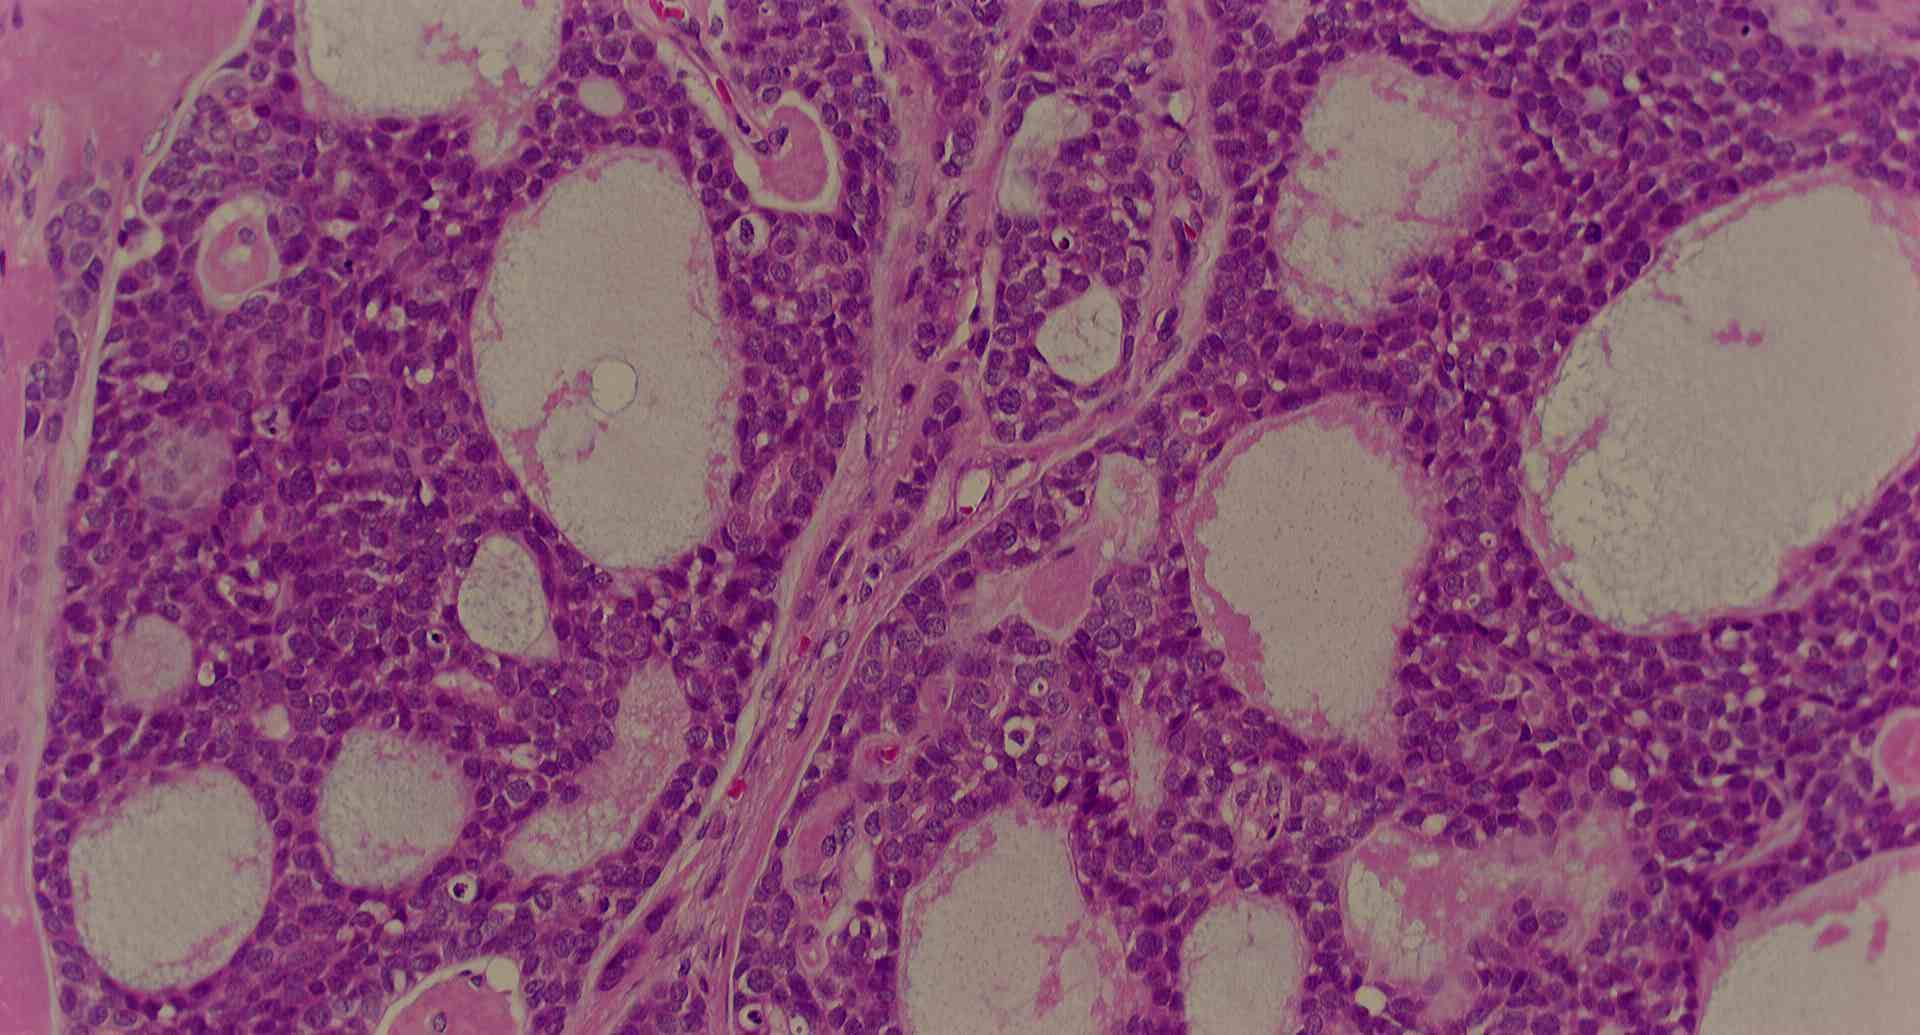

標本16

標本16の説明